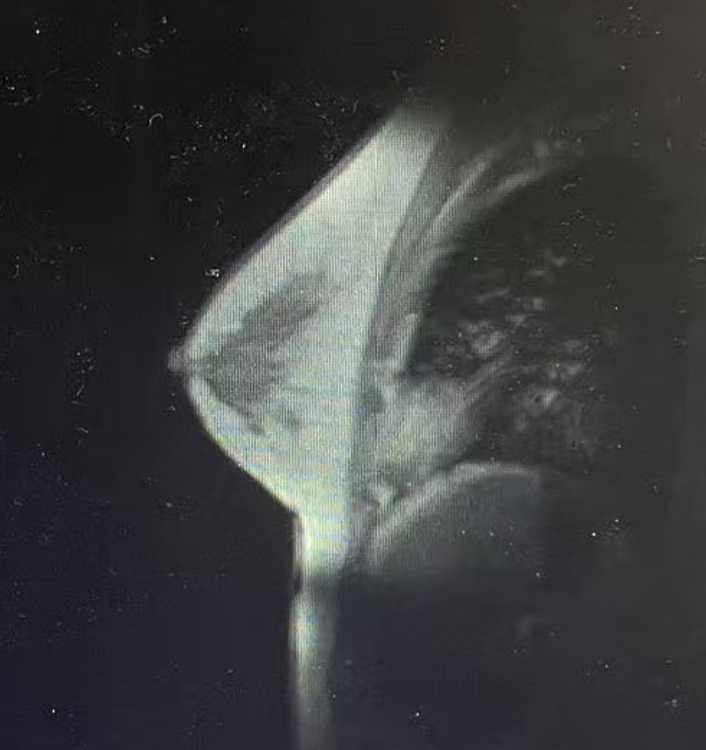

·CT

1、右乳后上方结节影,伴右侧腋下多枚淋巴结,建议乳腺核磁MRI平扫+增强进一步检查;

2、右肺下叶及左肺下叶胸膜下少许间质增生,或可能由肺坠积效应所致;

3、肝脏钙化灶

4、胸腰椎轻度退行性变。

图4 CT结果